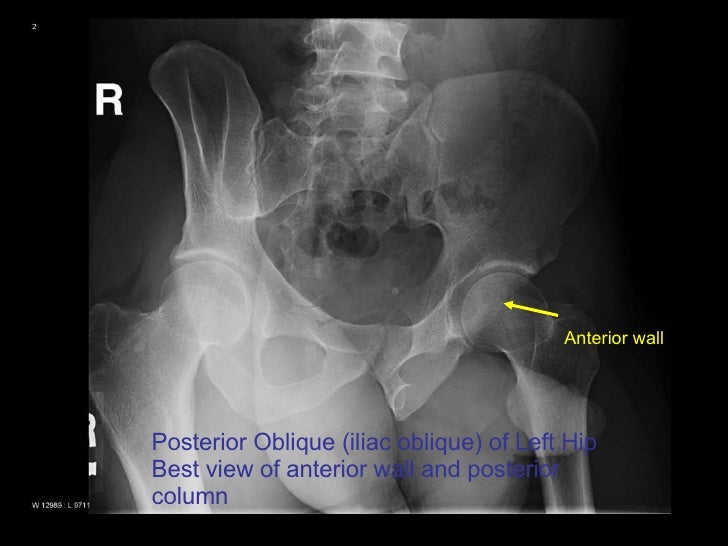

Hip X Ray Judet View . Pelvis ap purpose and structures shown clear image. Judet's views are standard radiographic projections which are employed in patients with acetabulum fractures. This page is dedicated to all aspects of judet view technique. The pelvis series examines the main pelvic ring, obturator foramina, sacroiliac joints, symphysis pubis, acetabulum, sacral foramina, and the proximal femur. The hip series is comprised of an anteroposterior (ap) and lateral radiograph of the hip joint. The series is requested for a myriad of.